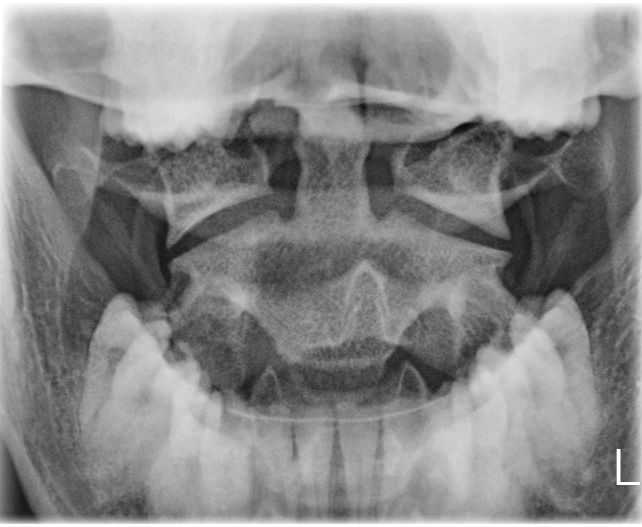

Dens

index.png

Indikation

Fraktur

Lagerung

Rückenlage

Kinn anziehen, bis obere Zahnreihe und Hinterhauptshöcker senkrecht zueinanderstehen

Mund weit geöffnet

Zentralstrahl

Querstrahl: Mundwinkel

Längsstrahl: Medianebene

Einblendung

seitlich ca. 1 QF neben Mundwinkel,

cranial: Spina nasalis

Bemerkung

auch sitzend am Stativ möglich

Qualitätskriterien

Bissebene und Unterkante des Hinterhaupts sollen sich überdecken. Der Dens ist mittelständig: gleicher Abstand zum aufsteigenden Ast des Unterkiefers beidseits. Weitgehend überlagerungsfreie Darstellung des Atlas und des Axis mit Dens. Gut einsehbares Atlantookzipital- und Atlantoaxialgelenk. Der vordere und der hintere Atlasbogen überlagern den Dens.